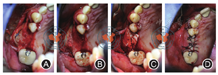

术前抽血25 ml制备富血小板纤维蛋白(platelet-rich fibrin,PRF)膜以备用。常规消毒后,局麻下沿25、26牙槽嵴顶偏颊侧做"梯形"切口,翻瓣,开窗后剥离上颌窦膜,推余留骨质向窦腔,放置1片PRF膜,充填骨粉(1.5 g,Bicon,美国),放置胶原膜(2.0 cm × 2.5 cm,海奥口腔修复膜,烟台)后覆盖PRF膜,严密缝合创口(图2)。术后CBCT示:25区骨质较厚,约6.3 mm,骨粉较少;26骨粉高度约10 mm。植骨区与窦腔内炎症区分界明显,窦膜完整(图3)。

注:图2A为沿25、26牙槽嵴顶偏颊侧做切口;图2B为上颌窦外提后充填骨粉;图2C为覆盖生物骨膜;图2D为缝合创口